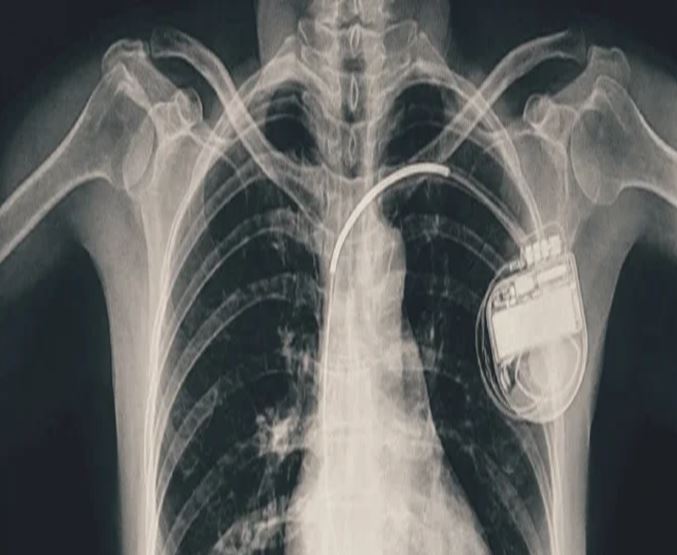

BMHRC के चिकित्सकों की बड़ी सफलता, डुअल चेंबर पेसमेकर से बची बच्ची की जिंदगी

भोपाल। भोपाल मेमोरियल अस्पताल एवं अनुसंधान केंद्र (बीएमएचआरसी) के कार्डियोलॉजी विभाग ने एक दुर्लभ और चुनौतीपूर्ण चिकित्सा उपलब्धि हासिल की है। यहां 13 वर्ष की गैस पीड़ित आश्रित बालिका को इमरजेंसी में डुअल चेंबर पेसमेकर लगाकर उसकी जान बचाई गई। अब बालिका की हालत बेहतर है और उसे अस्पताल से छुट्टी दे दी गई है। यह प्रक्रिया सहायक प्रोफेसर डॉ. अमन चतुर्वेदी और उनकी टीम द्वारा सफलतापूर्वक की गई।

तीन वर्ष की आयु में दिल में था छेद

बीएमएचआरसी के कार्डियोलॉजी विभाग के सहायक प्रोफेसर डॉ. अमन चतुर्वेदी ने बताया कि यह मरीज जन्म से ही हृदय रोग से पीड़ित थी। तीन वर्ष की आयु में उसके दिल में छेद (congenital heart defect) का ऑपरेशन किया गया था। ऑपरेशन के बाद उसे हार्ट ब्लॉक हो गया यानी हृदय की धड़कन असामान्य रूप से धीमी हो गई। इसके कारण उसे चक्कर आना, आंखों के सामने अंधेरा छा जाना जैसी परेशानियां होने लगीं।हार्ट ब्लॉक की स्थिति में, बचपन में ही उसे एपिकार्डियल पेसिंग (epicardial pacing) डिवाइस लगाई गई। इस प्रक्रिया में पेसमेकर के तार हृदय की बाहरी सतह पर लगाए जाते हैं, जो आमतौर पर छोटे बच्चों में अपनाई जाती है, क्योंकि उनके हृदय का आकार छोटा होता है। इस डिवाइस की आयु लगभग 10 वर्ष होती है। डिवाइस की अवधि पूरी होने के बाद हाल ही में मरीज को फिर से वही लक्षण होने लगे। बीएमएचआरसी में जांच के बाद यह स्पष्ट हुआ कि अब उसे एक स्थायी और अधिक उन्नत पेसमेकर की आवश्यकता है। आपातकालीन स्थिति में टीम ने सफलतापूर्वक डुअल चेंबर पेसमेकर प्रत्यारोपित किया। इस जीवनरक्षक प्रक्रिया को अंजाम देने वाली टीम में कार्डियोलॉजी विभाग के सहायक प्रोफेसर डॉ. कपिलकांत त्रिपाठी, डॉ. नुपुर गोयल, मेडिकल ऑफिसर डॉ. अनुराग ठाकुर एवं अन्य सदस्य शामिल थे।

क्या होता है डुअल चेंबर पेसमेकर?

पेसमेकर एक छोटा उपकरण होता है, जो दिल की धड़कन को नियंत्रित करता है। यह दिल को सही गति से धड़कने में मदद करता है। सिंगल चेंबर पेसमेकर हार्ट के सिर्फ एक चेंबर को इलैक्ट्रिक सिग्नल देता है, जबकि डुअल चेंबर पेसमेकर दिल के दो भागों-ऊपरी (एट्रियम) और निचले (वेन्ट्रिकल) चेंबरों को दोनों को सिग्नल भेजता है, जिससे दिल की धड़कन और भी प्राकृतिक तरीके से चलती है। बच्ची के मामले में डुअल चेंबर पेसमेकर इसलिए लगाया गया क्योंकि उसकी स्थिति अधिक जटिल थी और बेहतर तालमेल के लिए दोनों चेंबर तक एकसाथ सिग्नल देना ज़रूरी था।

बच्चों या किशोरों में पेसमेकर लगाना बहुत मुश्किल

बीएमएचआरसी के चिकित्सकों का कहना है कि आमतौर पर पेसमेकर अधेड़ उम्र या बुज़ुर्गों को लगाए जाते हैं, लेकिन बच्चों में पेसमेकर लगाने के बहुत कम मामले सामने आते हैं। बच्चों या किशारों में ऐसा करना मुश्किल भी होता है क्योंकि बच्चों का दिल छोटा होता है, जिसमें उपकरण फिट करना कठिन होता है। साथ ही समय के साथ बच्चे का शरीर विकसित होता है, ऐसे में उपकरण का लंबी अवधि तक काम करना तकनीकी चुनौती बन जाता है। यही नहीं, पेसमेकर के तारों की लंबाई, फिटिंग और शरीर के भीतर उनकी स्थिति को भविष्य के हिसाब से बहुत सावधानी से तय करना होता है। बीएमएचआरसी की कार्डियोलॉजी टीम ने सभी सावधानी बरतते हुए मरीज को सुरक्षित रखा।